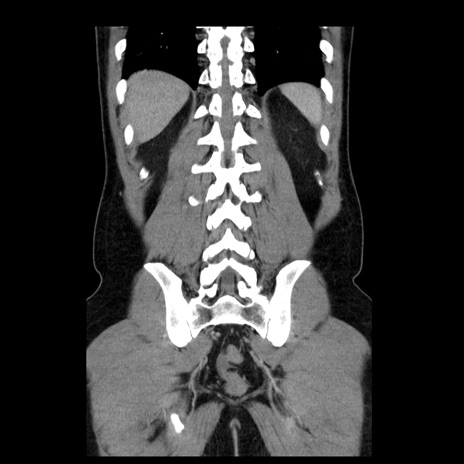

症例4(冠状断像)

【症例】30歳代男性

【主訴】腹痛、嘔吐

【現病歴】昨晩から突然の腹痛あり、その後嘔吐、軟便も出現。腹痛が改善しないため救急搬送となる。2日前にしめ鯖の食事歴あり。

【身体所見】意識清明、苦悶様、BP 135/90mmHg、BT 35.7℃、腹部:平坦、やや硬、心窩部〜臍部に自発痛、圧痛あり、筋性防御+、反跳痛-

【データ】WBC 8100、CRP 0.57